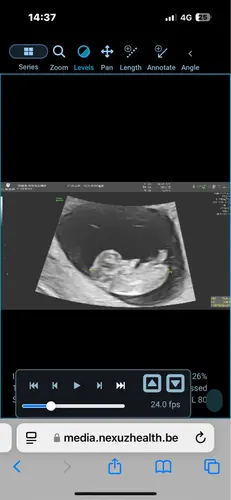

Ongeveer 5w5d en een kloppend hartje 🥰